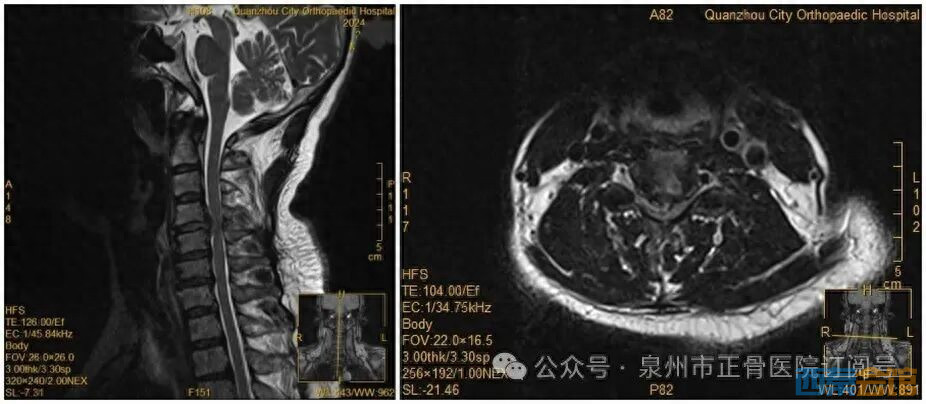

女子因手麻到医院就诊,拒绝医生颈椎手术建议,当晚翻身竟导致瘫..